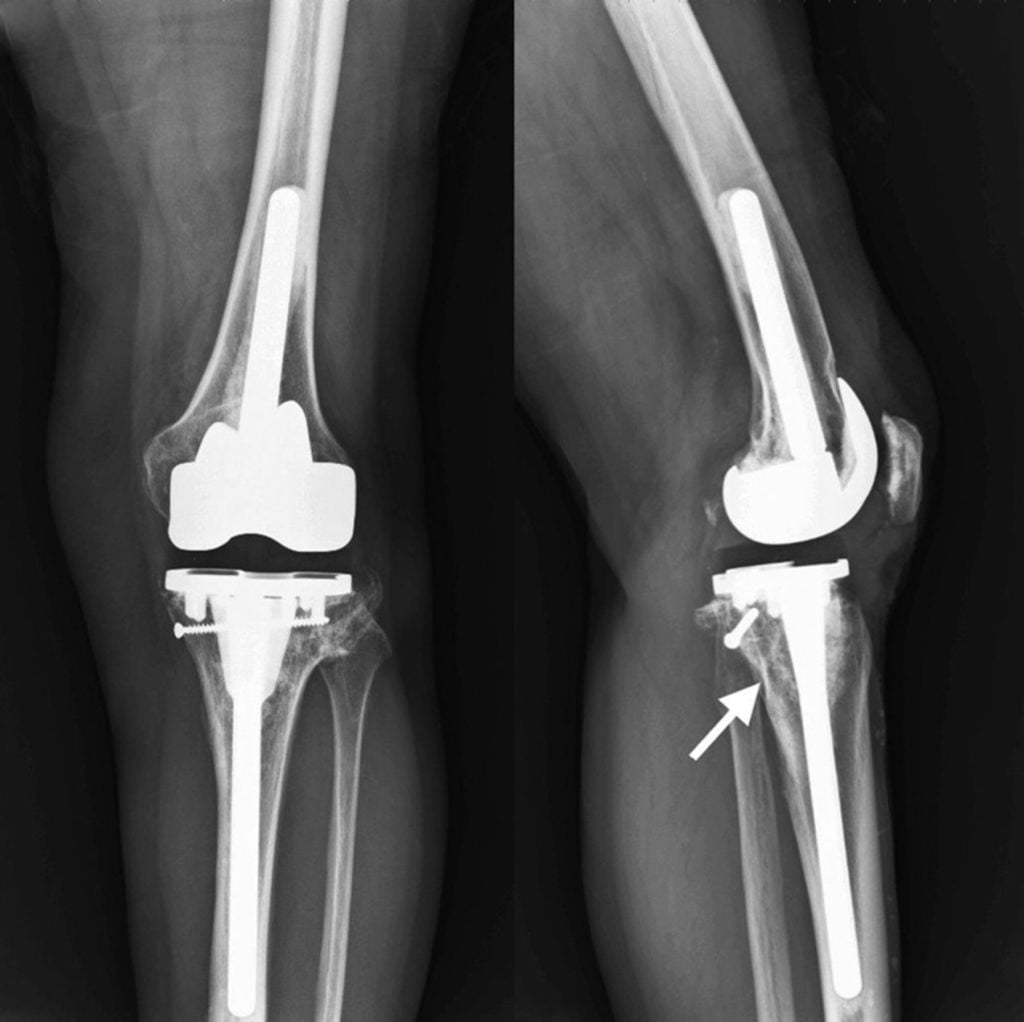

- бесцементный. Имплантаты имеют специальную текстурированную, пористую поверхность, через которую костная масса свободно прорастает во внутреннюю полость эндопротеза. Винты и штифты стабилизируют соединение, пока не произошло врастание. При установке приспособления требуется более длительный период восстановления. Не применяются для пациентов с остеопорозом, поскольку врастающая кость должна быть в хорошем состоянии.

Некоторыми хирургами используется гибридный метод с элементами обоих типов фиксации, однако он применяется при тазобедренном эндопротезировании.